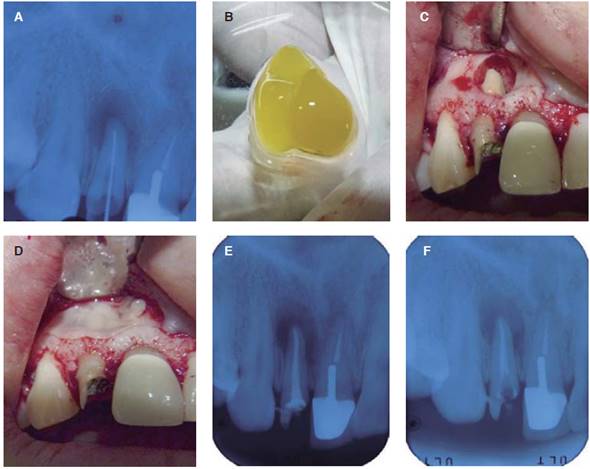

Figura 1 A) Radiografía periapical del incisivo lateral derecho mostrando una lesión periapical. B) Coágulo de fi brina obtenido y divide en dos. C) Osteotomía y visualización de la porción apical y apicectomía. D) PRF colocado dentro del defecto óseo y otro coágulo usado como barrera autóloga. E) Radiografía periapical finalizado el procedimiento. F) Radiografía periapical a los 30 días del procedimiento donde se observa una matriz ósea.

Después de un apropiado aislamiento del campo quirúrgico, el sitio quirúrgico es anestesiado utilizando 72 mg de lidocaína con epinefrina (1:80,000). Una incisión lineal fue realizada a lo largo de los surcos gingivales y se procedió a desprender un colgajo mucoperióstico. Una osteotomía fue realizada para alcanzar la porción apical del diente comprometido con la consecuente amputación de dicho ápice, debridamiento de la lesión, curetaje y remoción de tejido de granulación (Figuras 1C y 2C). Seguidamente se utilizó MTA VitalCem (Arequipa, Perú) para realizar la retroobturación y el coágulo de PRF fue colocado en el defecto óseo. Una barrera autóloga fue producida a partir del coágulo de PRF y fue colocada para cerrar el defecto óseo producido por la osteotomía (Figuras 1D y 2D). Los tejidos blandos fueron aproximados y suturados para provocar una cicatrización por primera intensión. Una radiografía periapical fue realizada inmediatamente terminado el procedimiento quirúrgico (Figuras 1E y 2E) y otra a los 30 días de la intervención (Figuras 1F y 2F).

No hubo complicaciones postoperatorias y la cicatrización fue satisfactoria. Al control radiográfico se sugiere la formación de matriz ósea en el defecto óseo a los 30 días para ambos pacientes.